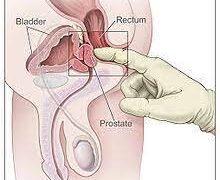

Read moreডা. মিজানুর রহমান কল্লোল প্রস্টেট হচ্ছে ছোট একটি গ্রন্থি, যা পুরুষদের থাকে। এটির অবস্থান মূত্রথলির ঠিক নিচে। প্রস্টেট ঘিরে রাখে...